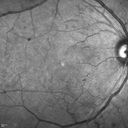

Proliferative Diabetic Retinopathy - Moderate - mild NVD with NVE 549 viewsFA shows leakage from neovascularization and dark areas in periphery from non-perfusion     (0 votes)

Proliferative Diabetic Retinopathy - Moderate - mild NVD with NVE 512 viewsFA shows leakage from neovascularization and dark areas in periphery from non-perfusion     (0 votes)